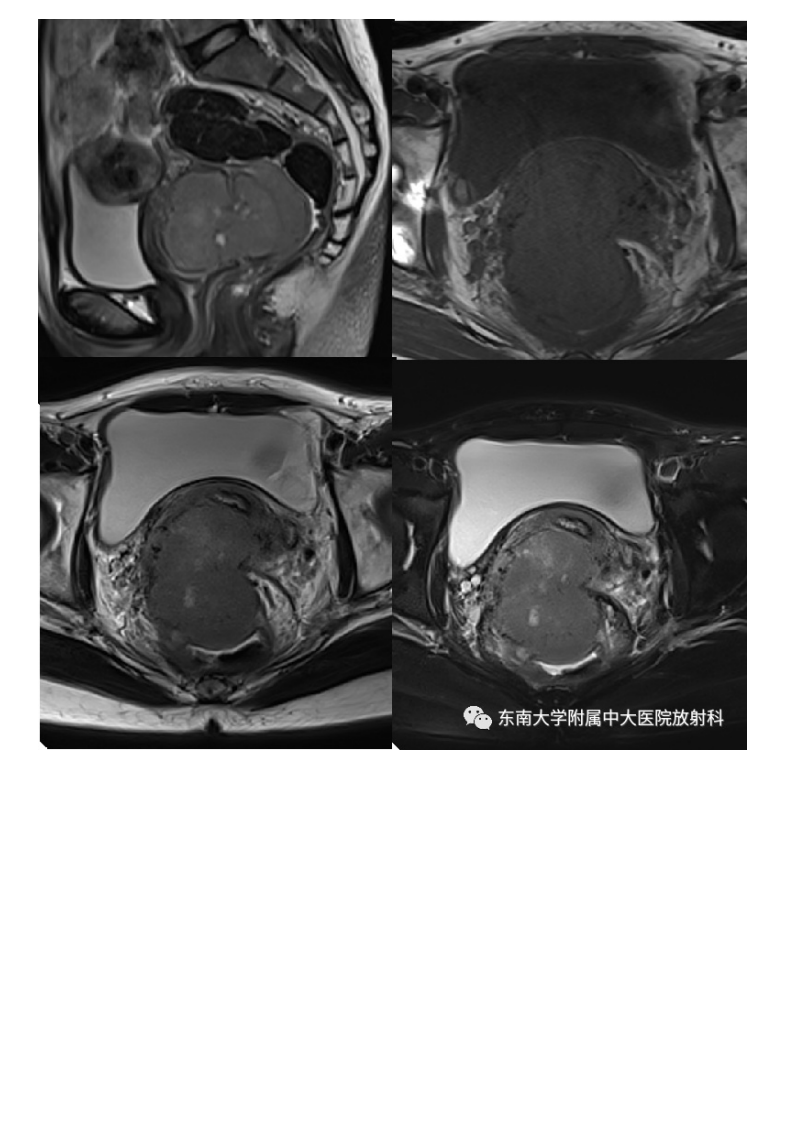

20210525_2【晨读结果公布】2021.05.24生殖系统疾病——病例1病理倾向于炎性假瘤;病例2:子宫内膜样癌;病例3:宫颈富细胞性肌瘤.pdf